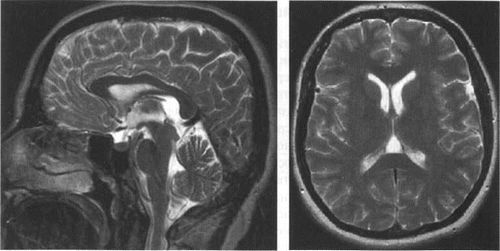

Мал. 3.8. Кістозна трансформація IV шлуночка. МРТ.

а - в режимі Т1, сагітальній площині. IV шлуночок має округлу форму, різко розширено. Черв'як мозочка гипоплазирована, мигдалини розташовуються нижче рівня великого потиличного отвори.

Є висхідний мозжечково-транстенторіальное вклинение з компресією четверохолмной цистерни. Міст і довгастий мозок зміщені вперед.

б - в режимі Т1, коронарна площину. Розширення порожнини IV шлуночка виражено нерівномірно, ліва гемісфер мозочка атрофована в більшій мірі.